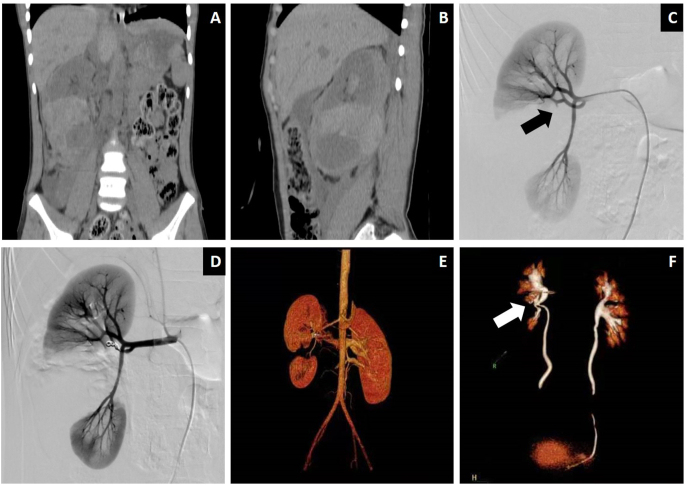

Fig. 2.

Images of a representative case with renal injury (AAST Grades V).

(a, b) Primary CT scan revealed a completely shattered right kidney. (c) DSA showed vessel disruption located at the segmental arteries (black arrow). (d) The involved arteries were embolized by GS plus coils. (e, f) Follow up contrast-enhanced CT along with volume reconstruction showed a completely shattered right kidney and renal pelvis stenosis (white arrow).